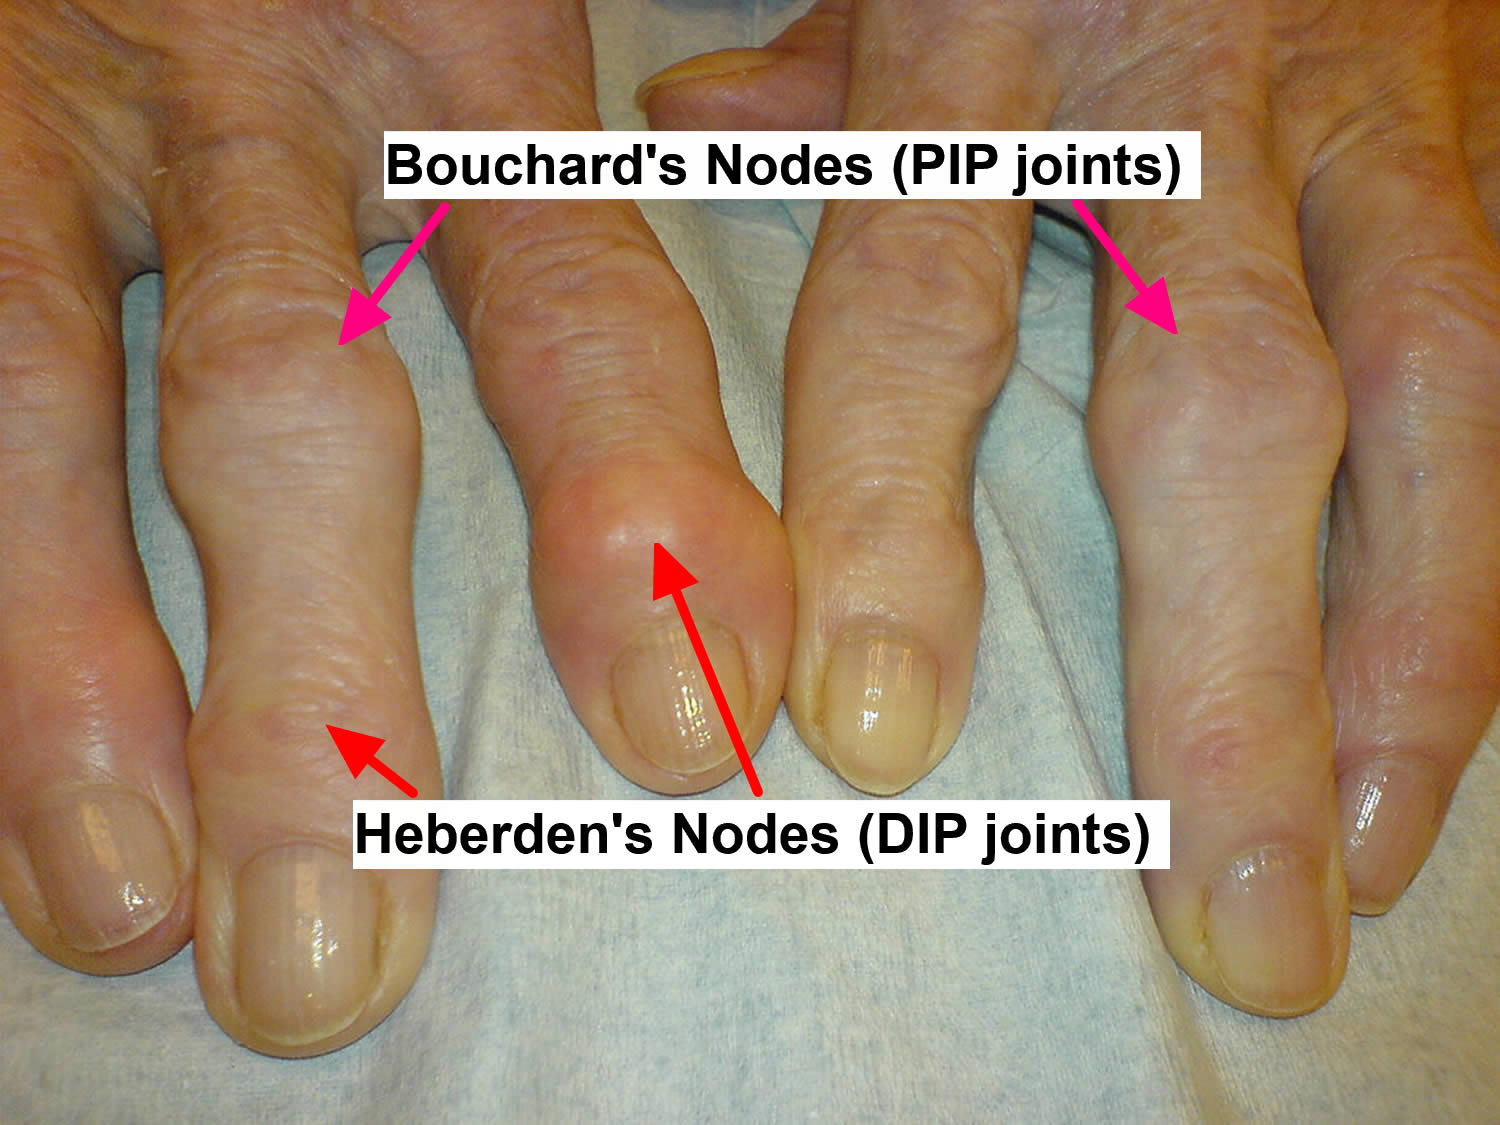

Arthritis Pictures

Bouchard Nodes What Are They Causes Signs Symptoms And More

Finger Nodes

Heberden Nodes

Heberden Nodes